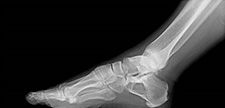

Benzer bir lezyon subungual (tırnak altında gelişen) ekzositozdur. Ayağın birinci parmağının altında sık görülür. Geçmişinde bir travma hikayesi vardır. Tırnağı kaldırdığında veya ağrı oluştuğunda çıkartılması gerekir. Hikaye ve yerleşim yerideğerlendirilerek gerçek osteokondromdan ayırt etmek gerekir.